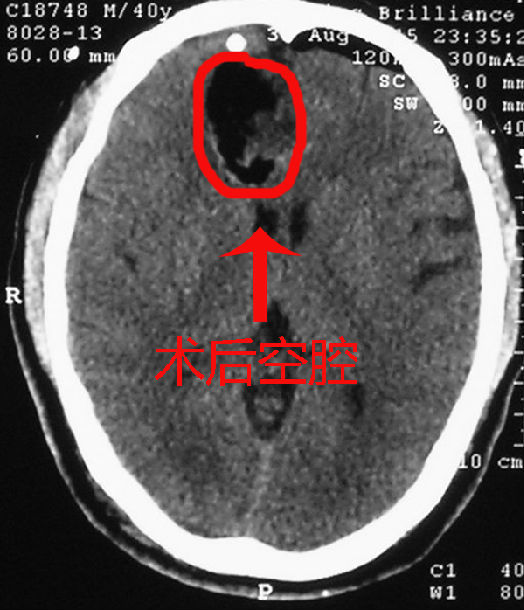

右侧单额开颅额叶胶质瘤切除